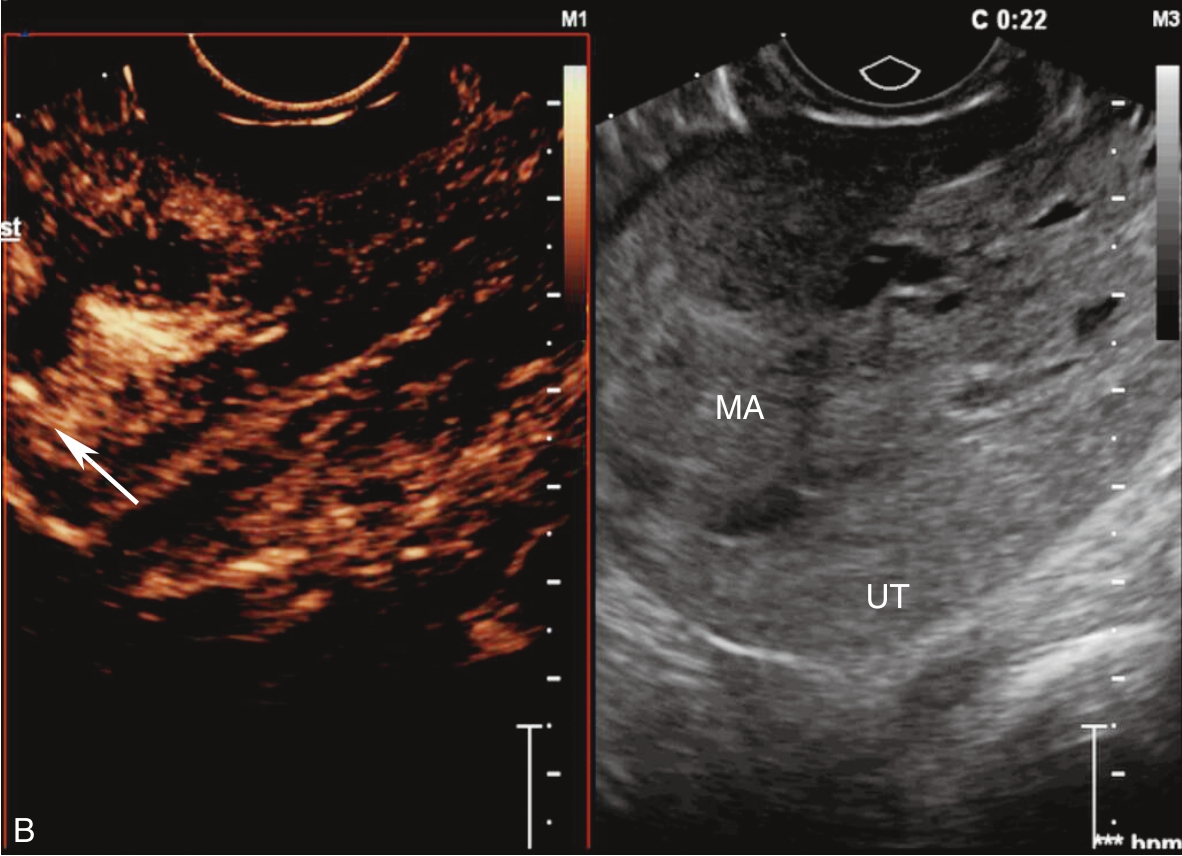

经静脉超声造影见图3-10-2及ER 3-10-1。注入造影剂后11s,宫腔内不均质稍强回声团块开始出现增强(图3-10-2A箭头所示),稍早于子宫肌层增强;注入造影剂后22s,团块根蒂似附着于宫腔上段宫底处(图3-10-2B箭头所示);注入造影剂后26s,宫腔内团块呈高增强,且其内造影剂分布不均匀(图3-10-2C箭头所示);注入造影剂后43s,宫腔内团块造影剂消退晚于子宫肌层(图3-10-2D箭头所示)。

图3-10-2 经静脉超声造影声像图

A.注入造影剂后11s;B.注入造影剂后22s;C.注入造影剂后26s;D.注入造影剂后43s。UT:子宫;MA:肿物。